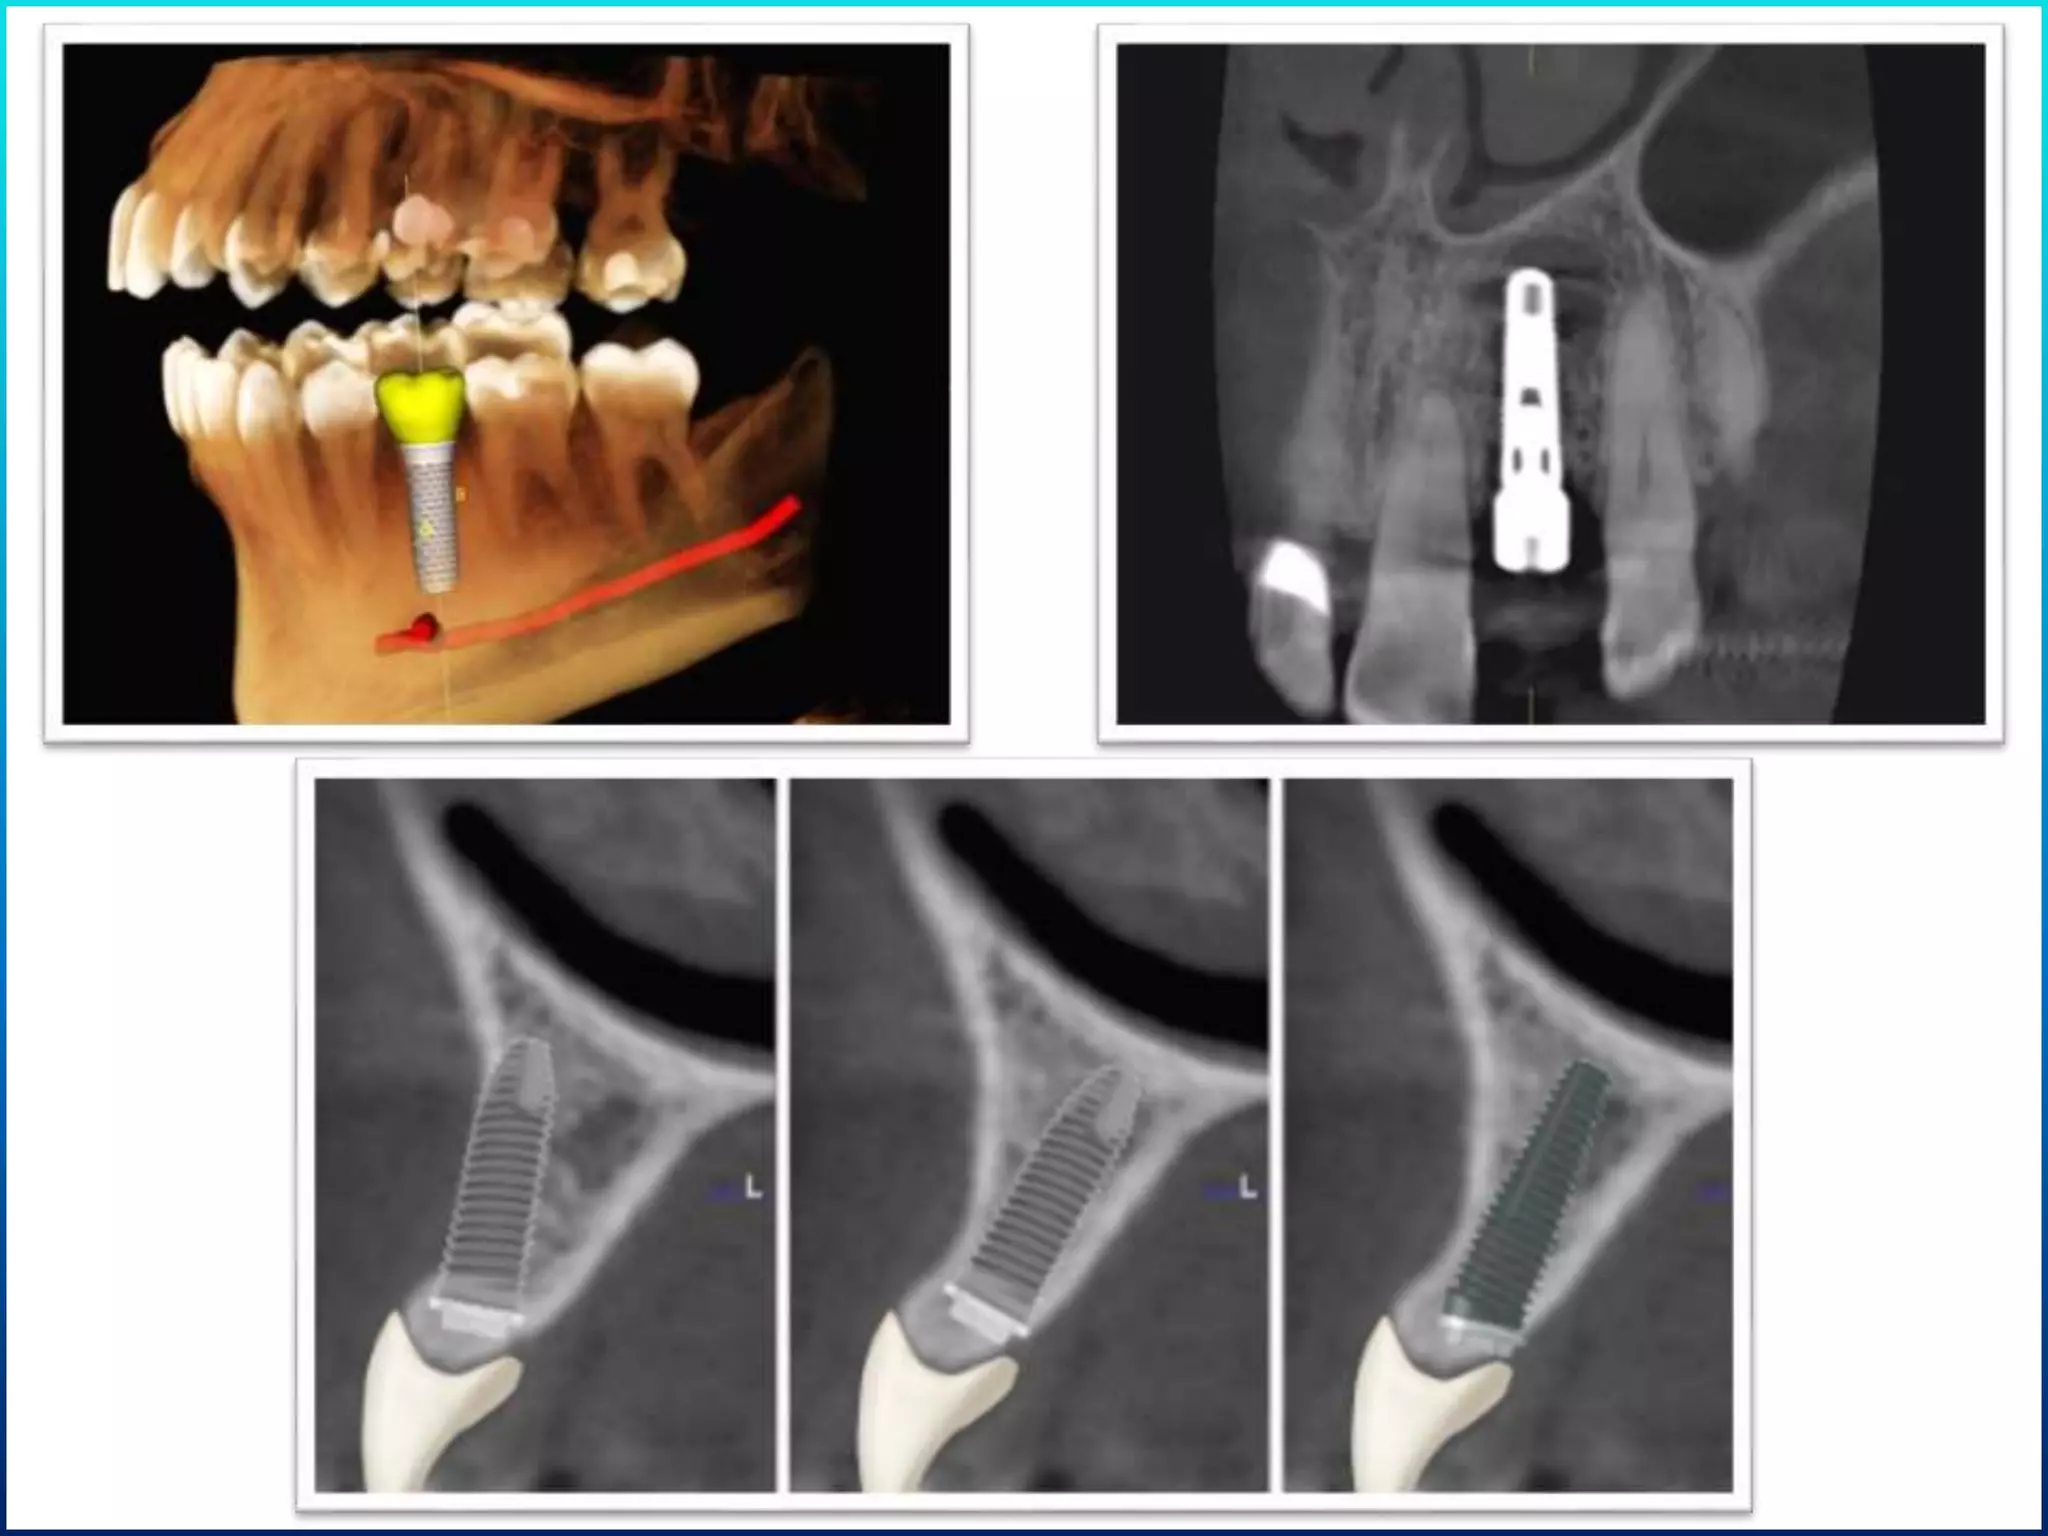

Available bone angulation

• In posterior mandible submandibular fossa mandates implant placement with

increasing Angulation as it progresses distally 15,20,25 degrees and so on.